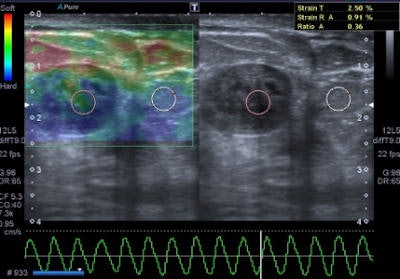

Freehand ultrasound, or compression elastography ("strain elastography"), is based on the application of a compressive force to the breast and on the measurement of the shape-deforming effect, thus providing a value of lesion stiffness compared with that of surrounding tissues, the authors wrote. A slight manual compression/decompression is applied using a conventional transducer, or the deformation may be determined by respiratory movements.

"The technique allows only for qualitative and semiquantitative assessments of a lesion because the force exerted by manual compression is unknown to the equipment, thus allowing only the calculation of the deformability ratio (strain ratio) and not the absolute elasticity," Ricci wrote and colleagues.

The elastographic properties of fibroadenomas are controversial, because some studies report a substantial difference of fibrotic components than surrounding parenchyma, while other authors describe fibroadenomas as difficult to evaluate by color map because of similar elasticity to the breast gland, the authors noted. Strain ratio range reported by most authors for this specific type of lesion is around 2.1 ± 0.8. Fibroadenomas with larger fibrotic component and poor cellularity can have a suspicious color map, but in all cases the strain ratio is lower than malignant forms, they added.

Elastography is often used in "uncertain" lesions classified as BI-RADS 3 and 4, but it does not change medical protocol in cases of BI-RADS 1, 2, and 5 lesions. The mean elasticity score of color map was significantly higher for malignant lesions than for benign lesions (p < 0.001), usually mainly represented as blue areas in the color map.